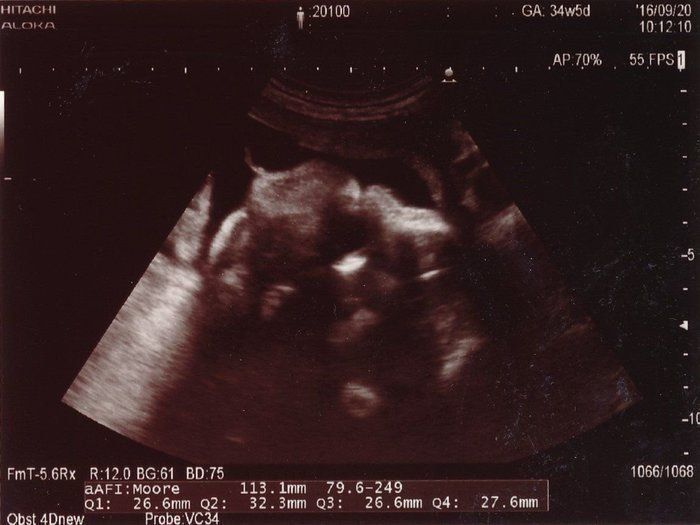

ベビオママさんの妊娠34週目のエコー写真 胎児が初めて2kg超え

一番白くはっきり写っているのは赤ちゃんの足の骨です。かなり太く、しっかりしてきました。小さく丸く写っているものがあったので、男の子であることも再確認できました。産院主催のお産の勉強会に参加して、いよいよ出産が近づいてきたと感じました。この時期には、夜中におなかが張ることが多くて、よく起きてしまいました。